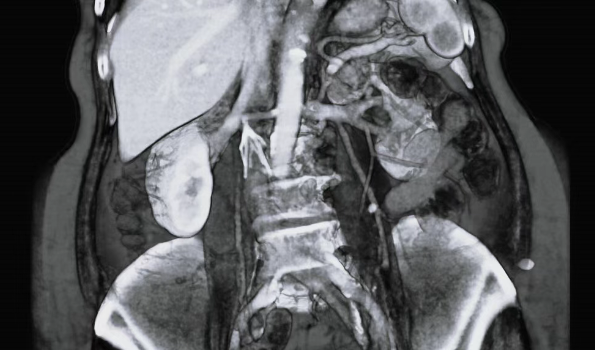

在近乎绝望时,李女士得知北京积水潭医院在血栓治疗领域经验丰富,尤其在困难滤器回收方面颇具口碑,于是怀着最后希望来到血管外科主任刘建龙的门诊。尽管团队拥有多年滤器回收经验,但检查后仍深感挑战巨大。患者滤器尖端已深入肾动脉、肾静脉与下腔静脉交汇的夹角区域,此处解剖结构复杂,毗邻重要器官和血管,且滤器支角紧邻腹主动脉,若不取出,血管损伤、下腔静脉堵塞风险极高。面对患者的期盼与信任,刘建龙决定将其收入院进一步治疗。

手术由血管外科主任刘建龙、副主任医师蒋鹏,普外科副主任高鹏骥,泌尿外科主任医师王海等组成手术团队联合上台主刀,各协作科室医护人员密切配合。在精密的腹腔镜下,手术团队精准定位切口,小心翼翼地暴露、阻断并切开下腔静脉,最终借助滤器回收套件成功完整取出滤器。